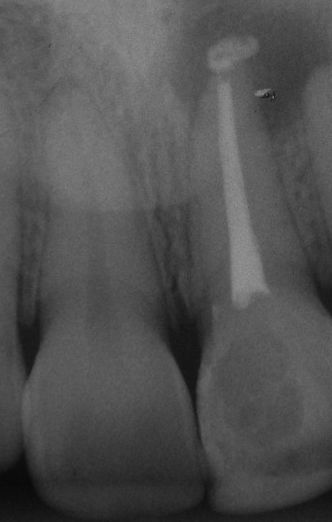

Paciente procurou a faculdade,pois relatava dor contínua,região de incisivos sup.,ao teste de vitalidade resultado foi negatico,ao exame radiografico foi constatado um tratamento endo insatisfatório dente 21,com espaço periapical alargado(área radiolúcida),foi realizado retratamento e diagnosticado como necro II.

Paciente sexo feminino ,18anos procurou a faculdade pois havia apresentado tumefação extra-oral à algum tempo na região dos incisivos sup. ,história de trauma no dente 21,mais ou menos 6 anos, teste de vitalidade-negativo ; ausência de fístula;exame ragiografico-área radiolucida na região periapical diagnóstico-necrose pulpar ;conduta:técnica de oregon modificada ,solução irrigadora hipoclorito a 2,5%,EDTA 17% ,uso do IAF; calen pmcc ;obturação :condensação lateral ;blindagem C.I.V.

Obs. extravasamento acidental de cimento,proservar!prognóstico favorável